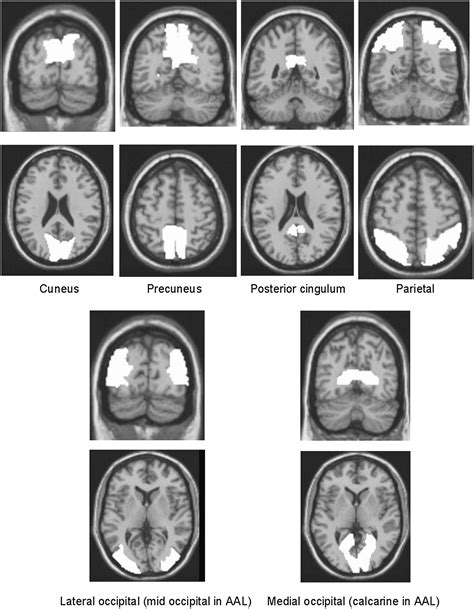

As the cis is influenced by concomitant alzheimer's disease (ad. It can help to identify dementia with lewy bodies (dlb) and distinguish it from alzheimer's disease and other dementias. This gives the appearance of a discrete 'island' of comparatively more intense uptake in the region of the posterior cingulate gyrus. Web the cingulate island sign is a highly specific radiological sign described in dementia with lewy bodies. Web the cingulate island sign is a supportive biomarker in discriminating dlb from ad according to the diagnostic criteria and refers to the relative preservation of posterior cingulate cortex metabolism, in relation to the parietal and occipital lobes. Web the cingulate island sign (cis) refers to the relative sparing of metabolism in the posterior cingulate cortex (pcc) and represents an important biomarker in distinguishing dementia with lewy bodies (dlb) from alzheimer disease (ad). Web a cingulate island sign (arrow) is produced when the posterior cingulate gyrus has normal metabolism and there is abnormal reduced uptake in the adjacent parietal and occipital lobes. Web the cingulate island sign (cis) is the most recently identified specific feature of dlb for a differential diagnosis.

Web the cingulate island sign is a highly specific radiological sign described in dementia with lewy bodies. Web the cingulate island sign is a highly specific radiological sign described in dementia with lewy bodies. Web the cingulate island sign (cis) refers to the relative sparing of metabolism in the posterior cingulate cortex (pcc) and represents an important biomarker in distinguishing dementia with lewy bodies (dlb) from alzheimer disease (ad). Web the cingulate island sign (cis) is the most recently identified specific feature of dlb for a differential diagnosis. It can help to identify dementia with lewy bodies (dlb) and distinguish it from alzheimer's disease and other dementias. This gives the appearance of a discrete 'island' of comparatively more intense uptake in the region of the posterior cingulate gyrus. Web the cingulate island sign is a supportive biomarker in discriminating dlb from ad according to the diagnostic criteria and refers to the relative preservation of posterior cingulate cortex metabolism, in relation to the parietal and occipital lobes. Web a cingulate island sign (arrow) is produced when the posterior cingulate gyrus has normal metabolism and there is abnormal reduced uptake in the adjacent parietal and occipital lobes. As the cis is influenced by concomitant alzheimer's disease (ad.